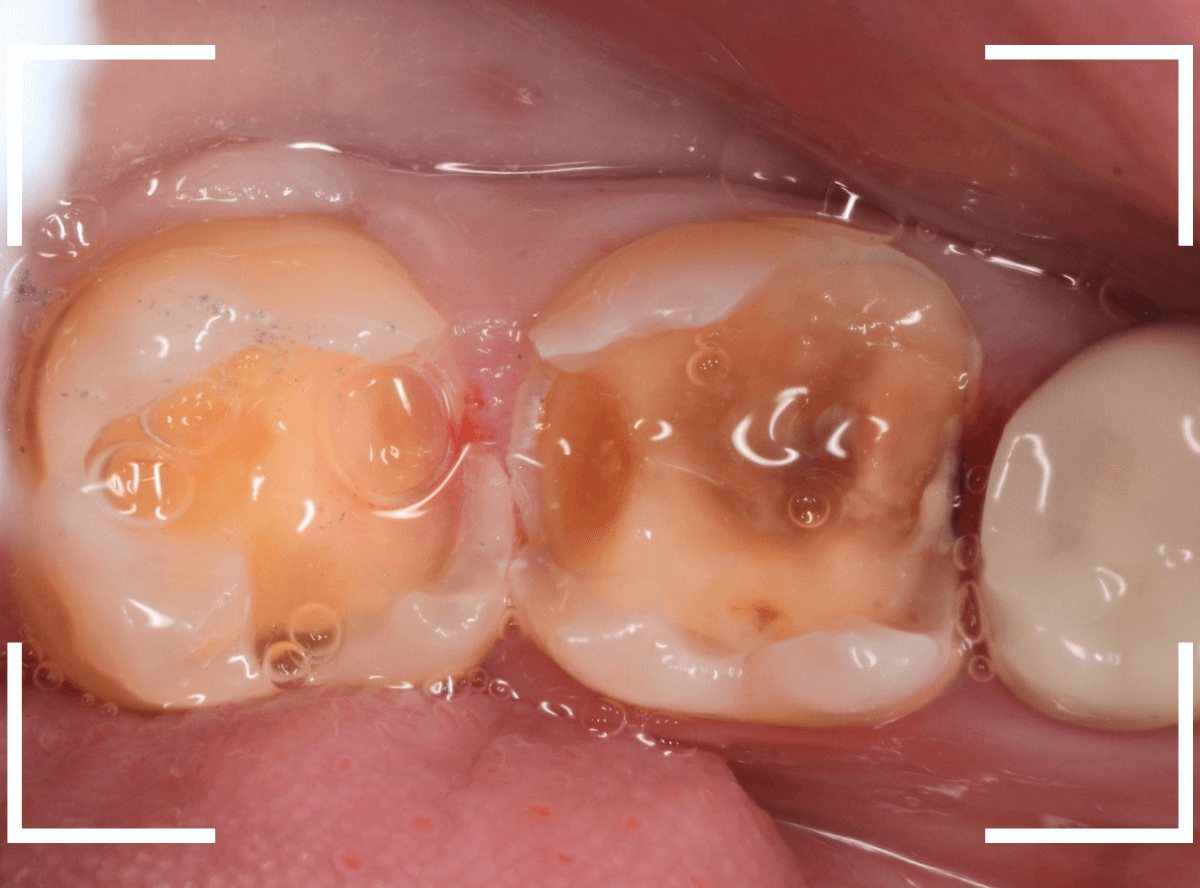

金属を外して、ある程度虫歯を除去したところです。

金属の下にしいてあるセメントも劣化してますので、中が虫歯になっていないかどうか、セメントも除去して調べます。

セメントまで除去したところです。

神経まで近い、かなり深い虫歯になっているのがわかります。

エナメル質付近はタービン、深めの虫歯の部分はコントラを使って、丁寧に虫歯を除去します。

8~9割ほどの虫歯が除去できたかというところですが、

赤く染色されている部分などがまだ虫歯が残っている部分です。